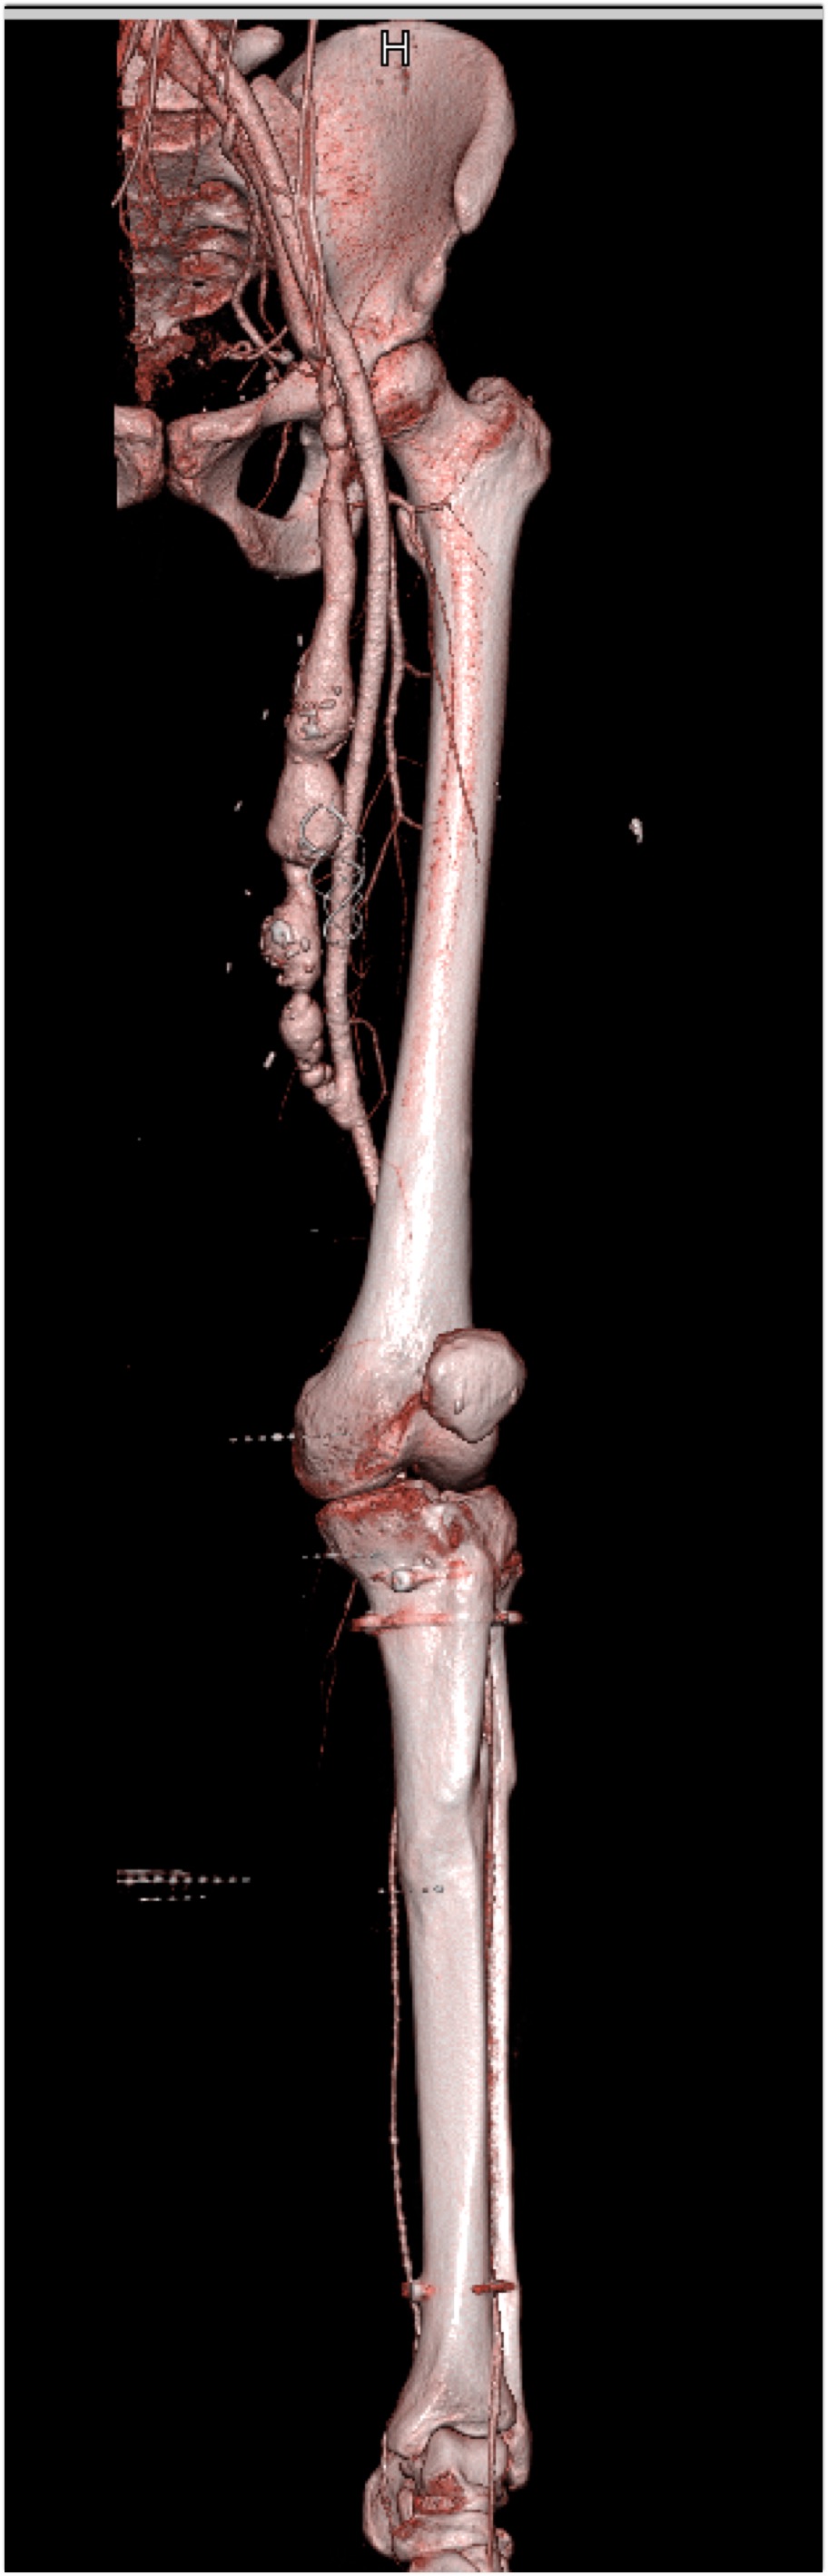

In this patient on dialysis for ESRD the best diagnosis is?

CTisus Quiz   CTisus Quiz

normal bypass graft

AV fistulae with aneurysms

vasculitis

infectious vascular disease